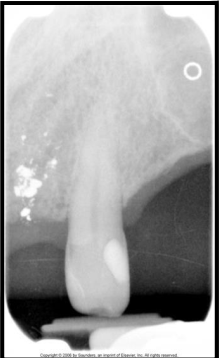

What are Gutta percha?

Gutta percha - clay-like thermoplastic material used in root canal therapy to obliterate the pullp canals.Â

appears radiopaque similar to base materials

less radiodense than metallic restorations.Â

What are silver points?

Silver points are used to obliterate pulp canals and appear more radiodense than gutta percha on a xray film.

used in endodontics